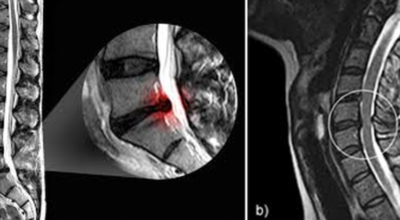

목디스크 증상이 나타날때 빨리 발견하여 비수술 치료를 받고 꾸준히 관리하는 것이 베스트이죠. 목디스크 환자 중 수술을 진행하는 환자는 2% 미만으로 현저히 적다고 해요. 수술을 진행하는 경우는 감각이 느껴지지 않는 마미증후군이나, 한쪽 다리가 눈에 띌 정도로 야윈 경우에만 진행하므로 올바른 자세 교정만으로도 충분히 호전될 수 있는 질병이죠. 목에 연관된 검사는 MRI나 CT를 이용해요. 그러나 전자의 경우 비용이 굉장히 비싸기 때문에 디스크 증세가 확실하다고 생각될 경우에만 선택적으로 하고 의무적으로 하는 건 아니니까 비용에 대해선 부담을 가지지 마시길 바래요.

목디스크 증상으로 인해 3개월 이상 약물이나 물리치료를 해도 효과가 없을 경우 수술을 고려해야 해요. 통증이 심해서 일상생활에 지장이 있거나, 신경증상이 악화되고 근력도 함께 줄어들 때와 큰 디스크가 탈출해 중추신경인 척수를 압박해 척수증이 발생하는 경우에도 수술을 고려할 수 있어요.